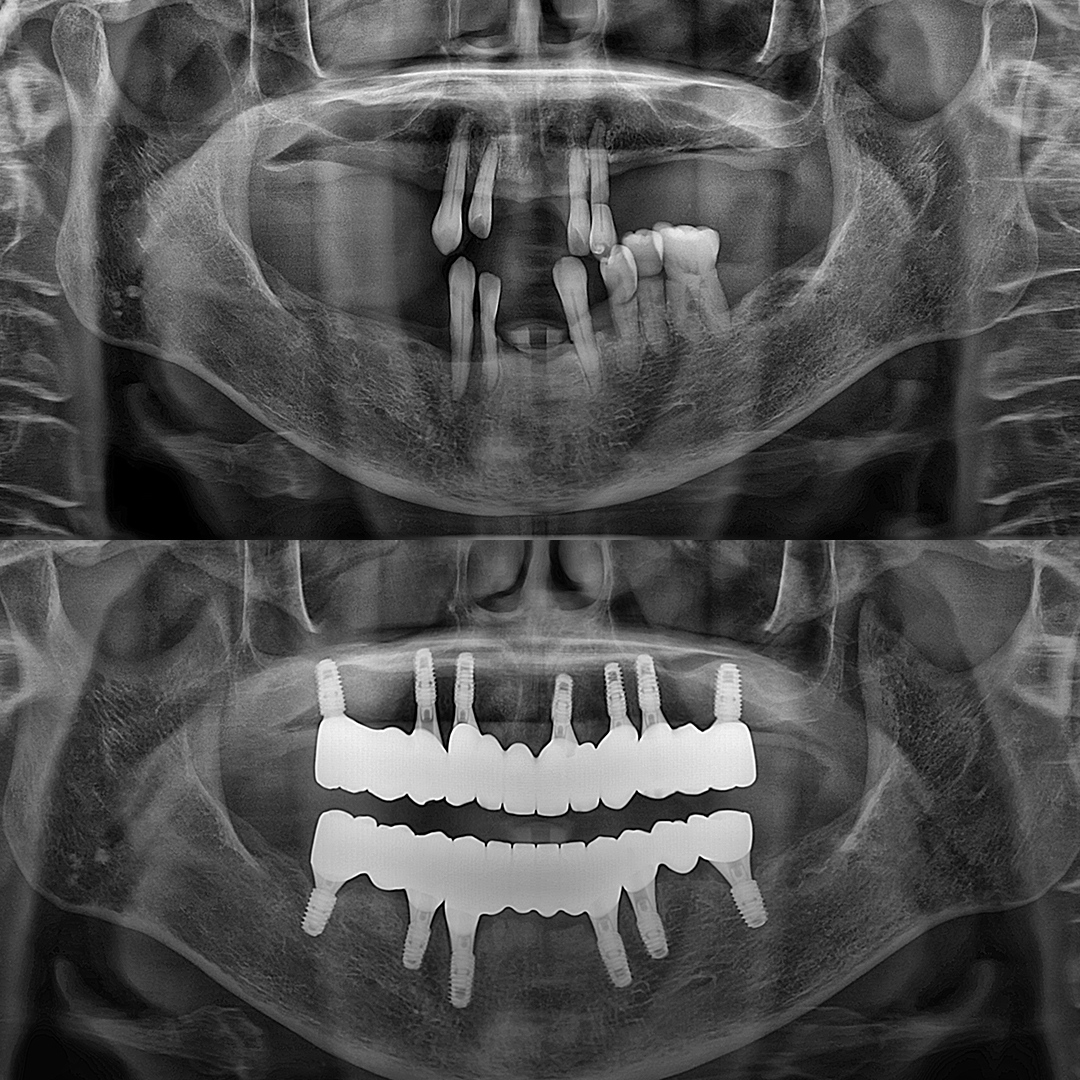

평균 악당 30분의 빠른 식립시간, 치료 케이스 다수 보유

전체 임플란트

상·하악 전체 치아를 대체하는 임플란트로 최소한의 식립을 통해

자연치아와 비슷한 기능을 수행할 수 있도록 합니다.